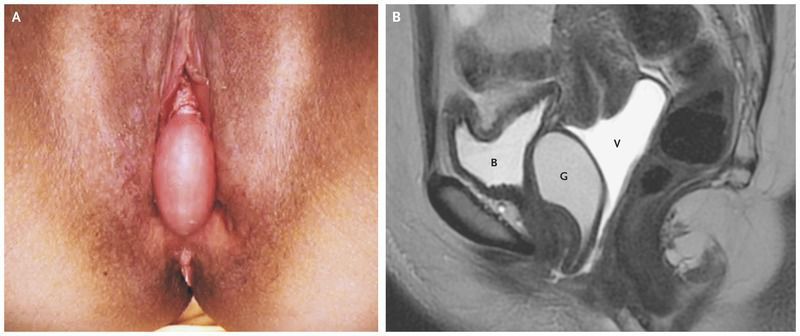

Gartner's duct is a remnant of mesonephric duct in females. Cystic dilatation of this remnant can lead to formation of a mass known as 'Gartner's duct cyst'. Gartner's duct cyst is usually asymptomatic. In adolescence, individuals may present with dysmenorrhea or difficulty in inserting tampon during menstruation. An association has been found between Gartner's duct cyst and anomalies of metanephric ducts. Reference: https://en.wikipedia.org/wiki/Gartner%27s_duct_cyst Image via: https://www.nejm.org/doi/full/10.1056/NEJMicm1609983 Reference: